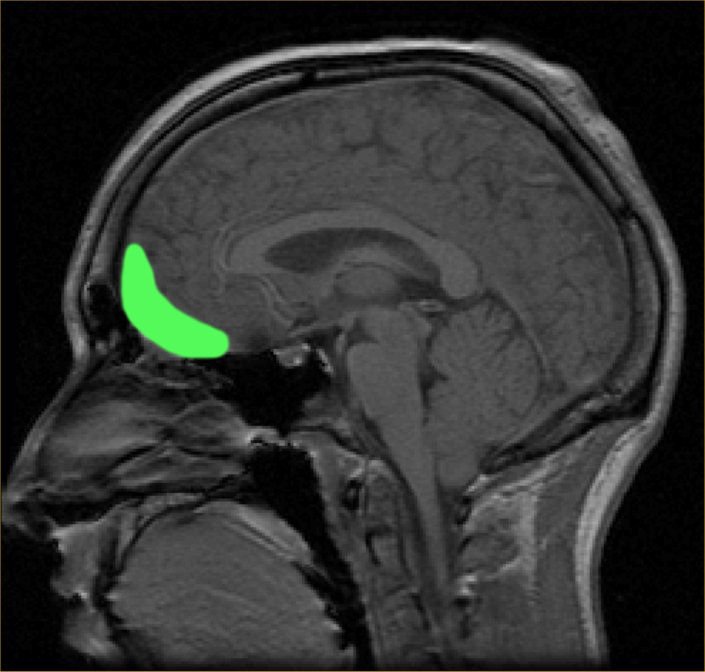

Doctors positioned the implants in different areas of the brain, including one close to the lateral portion of OFC (orbitofrontal cortex), which is right behind the eye. The OFC’s role is to make decisions, process emotions and regulate moods. And though OFC also contributes to depression, scientists haven’t considered it a target for stimulation.

The orbitofrontal cortex (OFC)

As theorized by the team, since the OFC interacts with other areas of the brain which connect aspects of emotion and mood, it can provide a more reliable benefit when stimulated. Little evidence has been found on whether non-invasive stimulation forms relating to the OFC can help the depressed or not.